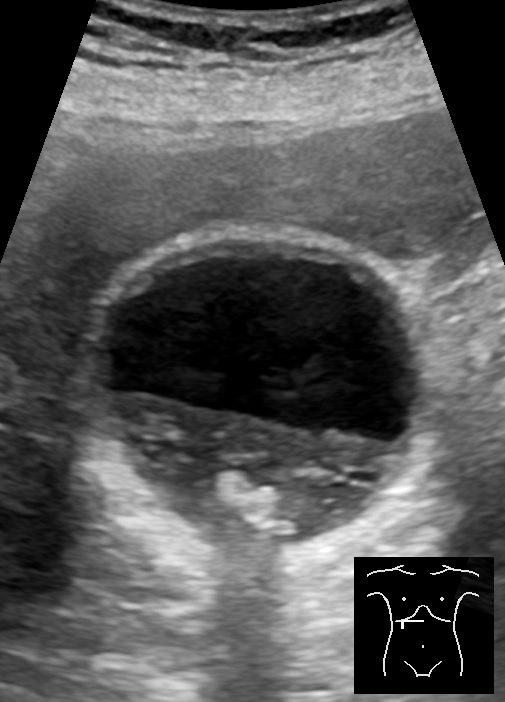

Ultrasound scan showing gallbladder sludge and multiple gallstones

Routine — First Line

Ultrasound Abdomen

The primary investigation for all gallbladder disease. Safe, quick, no radiation. Detects stones (even tiny ones), sludge, polyps, gallbladder wall thickening, pericholecystic fluid, and a dilated bile duct. Most patients need nothing further.